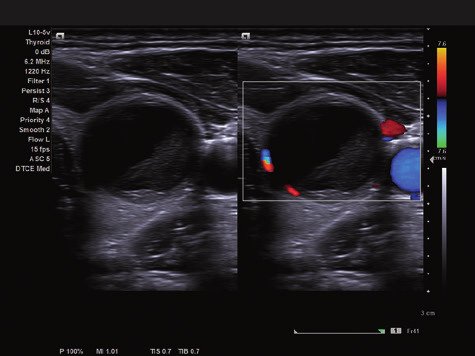

Das ACUSON NX2 Ultraschallsystem besitzt eine zukunftsfähige digitale Plattform mit nahezu unerreichter Bildqualität und sorgt für effiziente und zuverlässige Diagnosedaten. Die Vielseitigkeit des Ultraschallsystems wird mit einem großen kompatiblen Portfolio an Schallköpfen gedeckt, und so ist für jeden Anwendungsbereich etwas dabei. Die Bedienkonsole ist intuitiv aufgebaut und optimiert und erlaubt bis zu vier nach vorne gerichteten Schallkopfanschlüssen für eine enorme Effizienz und schnellen Workflow. So lassen sich bei der fetalen Bildgebung außergewöhnlich detailgetreue Darstellungen des Fetus im Gesicht zeigen oder durch die herausragende Farbdopplersensitivität bei der Darstellung der kleinen Gefäße des zystischen Schilddrüsenknotens kleinste Details erkennen. Weiterhin besticht das NX2 mit einfacher Aufrüstbarkeit bei wachsenden Anforderungen für Ihre zukünftigen Anwendungen und kompatible skalierbare Schallköpfe verringern ihren Kapitaleinsatz um bis zu 31 %.